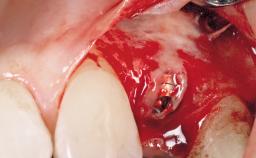

This 43-year-old male patient, a non-smoker, came to our practice because of a fracture of tooth 12 caused by a bicycle accident. Due to the combined para- and infrabony crown and root fracture, tooth extraction, and subsequent implant placement were suggested to the patient as the therapy of choice. The patient had high esthetic expectations with regard to the treatment outcome and asked for an immediate fixed provisional restoration. His individual esthetic risk profile summed up to a medium esthetic risk.

Placement Protocol Immediate implant placement

Loading Protocol Immediate

Retention Screw-retained Screw-retained